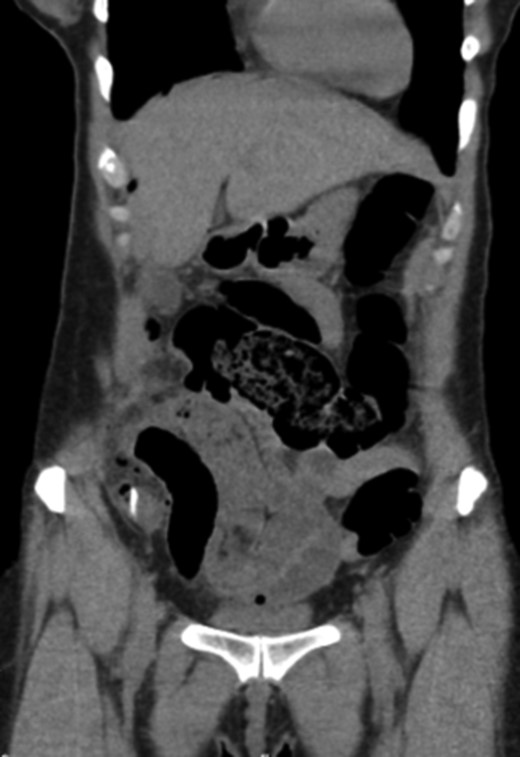

Blood tests revealed leukocytosis (14.500 white blood cells/μL) with neutrophilia (79%) and no C-reactive protein elevation; kidney and liver functions both were within normal range. Abdominal ultrasound showed some free fluid in the pelvis and a computed tomography scan was then performed and revealed a linear hyperdense foreign body located in distal ileum with intraperitoneal free air (Fig. 1). A presumed diagnosis of intestinal perforation was established, and patient was taken to the operating theatre for diagnostic laparoscopy.

CT scan evidencing a foreign body in distal ileum with intraperitoneal free air.